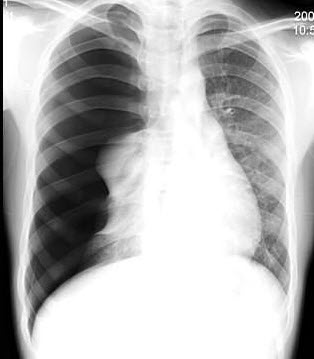

261、单项选择题

男,16岁,突感呼吸困难,大汗淋漓,胸片检查如图,最可能的诊断是()

A.右侧肺气肿

B.右侧肺部肿块

C.右侧气胸

D.右侧肺大泡

E.右侧肺挫伤